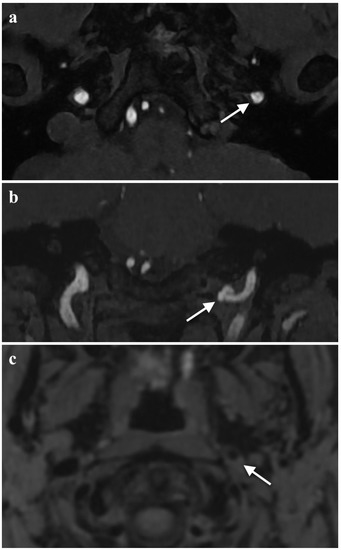

Acute Tongue Swelling as a Still Unexpected Manifestation of Internal Carotid Artery Dissection: A Case Report

The diagnosis of internal carotid artery dissection (ICAD) at the stage of local signs is essential in the prevention of the life-treating cerebral complication; however, making this diagnosis has significant difficulties. We present the case of a 36-year-old female with left ICAD with [...] Read more.

The diagnosis of internal carotid artery dissection (ICAD) at the stage of local signs is essential in the prevention of the life-treating cerebral complication; however, making this diagnosis has significant difficulties. We present the case of a 36-year-old female with left ICAD with asymmetric left-sided tongue swelling as an unusual and still unexpected symptom. The patient’s complaints at admission were left-sided numbness of the tongue and swallowing difficulties but its movements were intact. Despite the provided treatment for suspected angioedema, no improvement was noted. Additional examination revealed left-sided tongue weakness, ipsilateral soft palate palsy, paralysis and reduced tension of the left vocal fold, and left-sided Horner’s syndrome. Another suspected diagnosis was a dysfunction of the IX, X, and XII cranial nerves. A head MRI revealed an intramural hematoma of the left internal carotid artery. The radiologists suggested ICAD. The angio-MRI of the head arteries confirmed this diagnosis. The patient received dual antiplatelet therapy. The neuro-logopaedic therapy was also implemented. Currently, the patient’s symptoms are gradually improving with significantly better results on follow-up neuroimaging. Among the possible local symptoms of ICAD, proper attention should be paid to asymmetric swelling of the tongue as an atypical manifestation of damage to the hypoglossal nerve. Full article

Show Figures

Figure 1